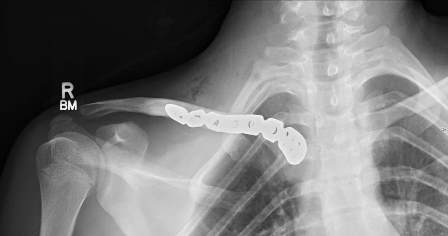

The patient underwent emergency open reduction through a longitudinal incision along the medial clavicle. Surgical exploration showed the floating fragment, which was rotated and had a partially stripped periosteal sheath (Fig. 4); its medial end had a rough surface, and did not have the appearance of a cartilaginous articular surface, which corresponded to a fracture through the medial physis of the clavicle. Gentle manoeuvres were performed to reduce the fragment. Anatomic reduction and fixation of the lateral fracture with a reconstructive plate (which crossed only the lateral fracture) resulted in reduction of the fracture. Radiographic confirmation of the reduction was obtained and stability was tested with gentle mobilization of the ipsilateral upper extremity and loading of the SC joint. After surgery, the patient was placed in a sling for 4 weeks: progressive resumption of movements and activities was then allowed. After surgery the patient was asymptomatic; examination showed symmetry of the clavicles and of the SC joints, painless and complete range of motion of the left shoulder. Radiographs showed complete consolidation at three months (Fig. 5). The patient has resumed full activities and sports without problems subsequently.

Fig. 5: Three months post-operative X-ray